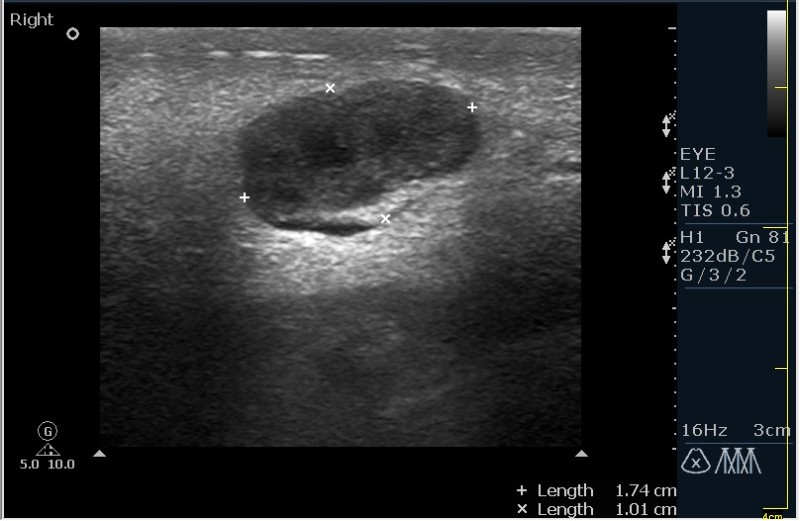

Мужчина 68 лет, направлен на УЗИ правой слюнной железы. Жалобы на пальпируемое, малоболезненное плотное образование за правым ухом.

Марио, что при компрессии образования -"зыбается" ли? т.е. образование солидное или жидкостное?

Солидное!!!! Я тоже ТАБ хотел сделать, но ЛОР заказал КТ... А какие мысли будут?

Первая мысль о очаговом воспалении, деструктивной фазе, но нет клиники.

Тумор?

Клиники нет, тумор на первом месте. В принципе КТ (или МРТ) заказывают для диффиренцировки зло/добро. Плюс посмотреть есть ли локальное растпространение. Но в данном случае я думаю УЗИ с ТАБ было бы достаточно.

Согласен! Поэтому в КТ отказал и настоял на ТАБ. Итак? Варианты?